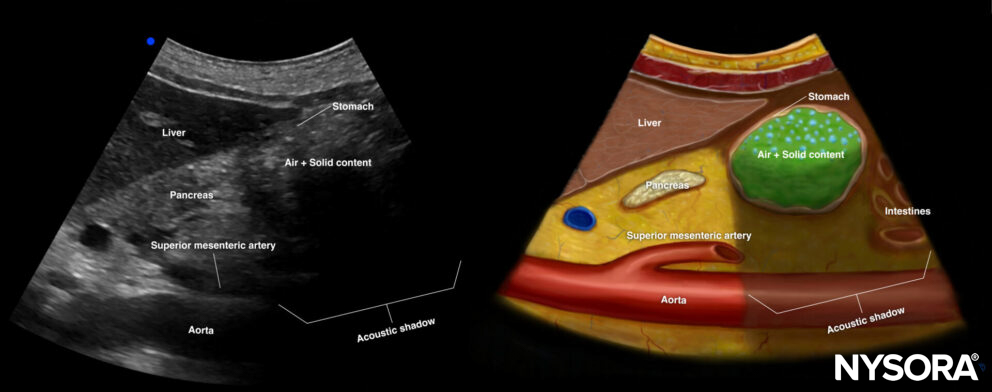

Solid content: Early phase

In the early phase after intake of solids, solid content is usually mixed with air, resulting in reflection of all the ultrasound beams, making it impossible to visualize the underlying structures. Mixed air and solid content is often described as the ‘frosted glass’ pattern. The wall of the antrum will be thin.

Ultrasound and Reverse Ultrasound Anatomy of a stomach with solid content in the early phase.